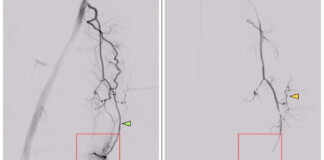

Oncologists Treat Patient’s Rare Cancer with Isolated Chemotherapy Delivery, Preventing Side-Effects

Sep 29, 2025

Inspiring